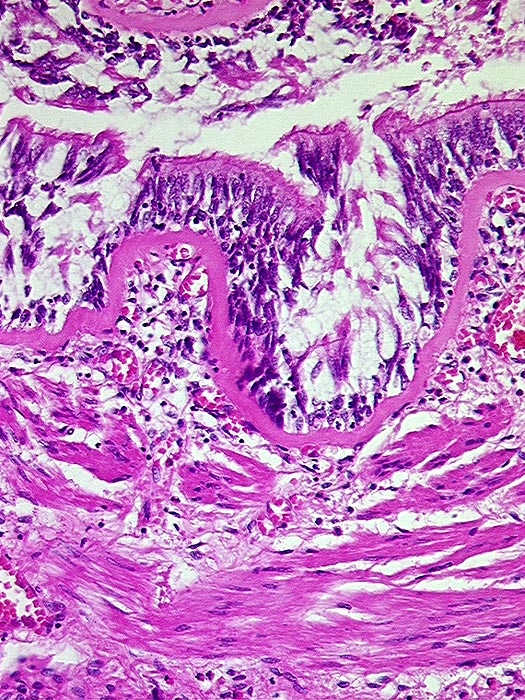

AP/ Asthma bronchiale

Asthma bronchiale

Bronchus

Normalbefund

Morphologie